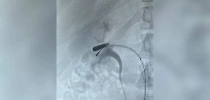

Московские врачи спали мужчину с плавающей по вене пулей